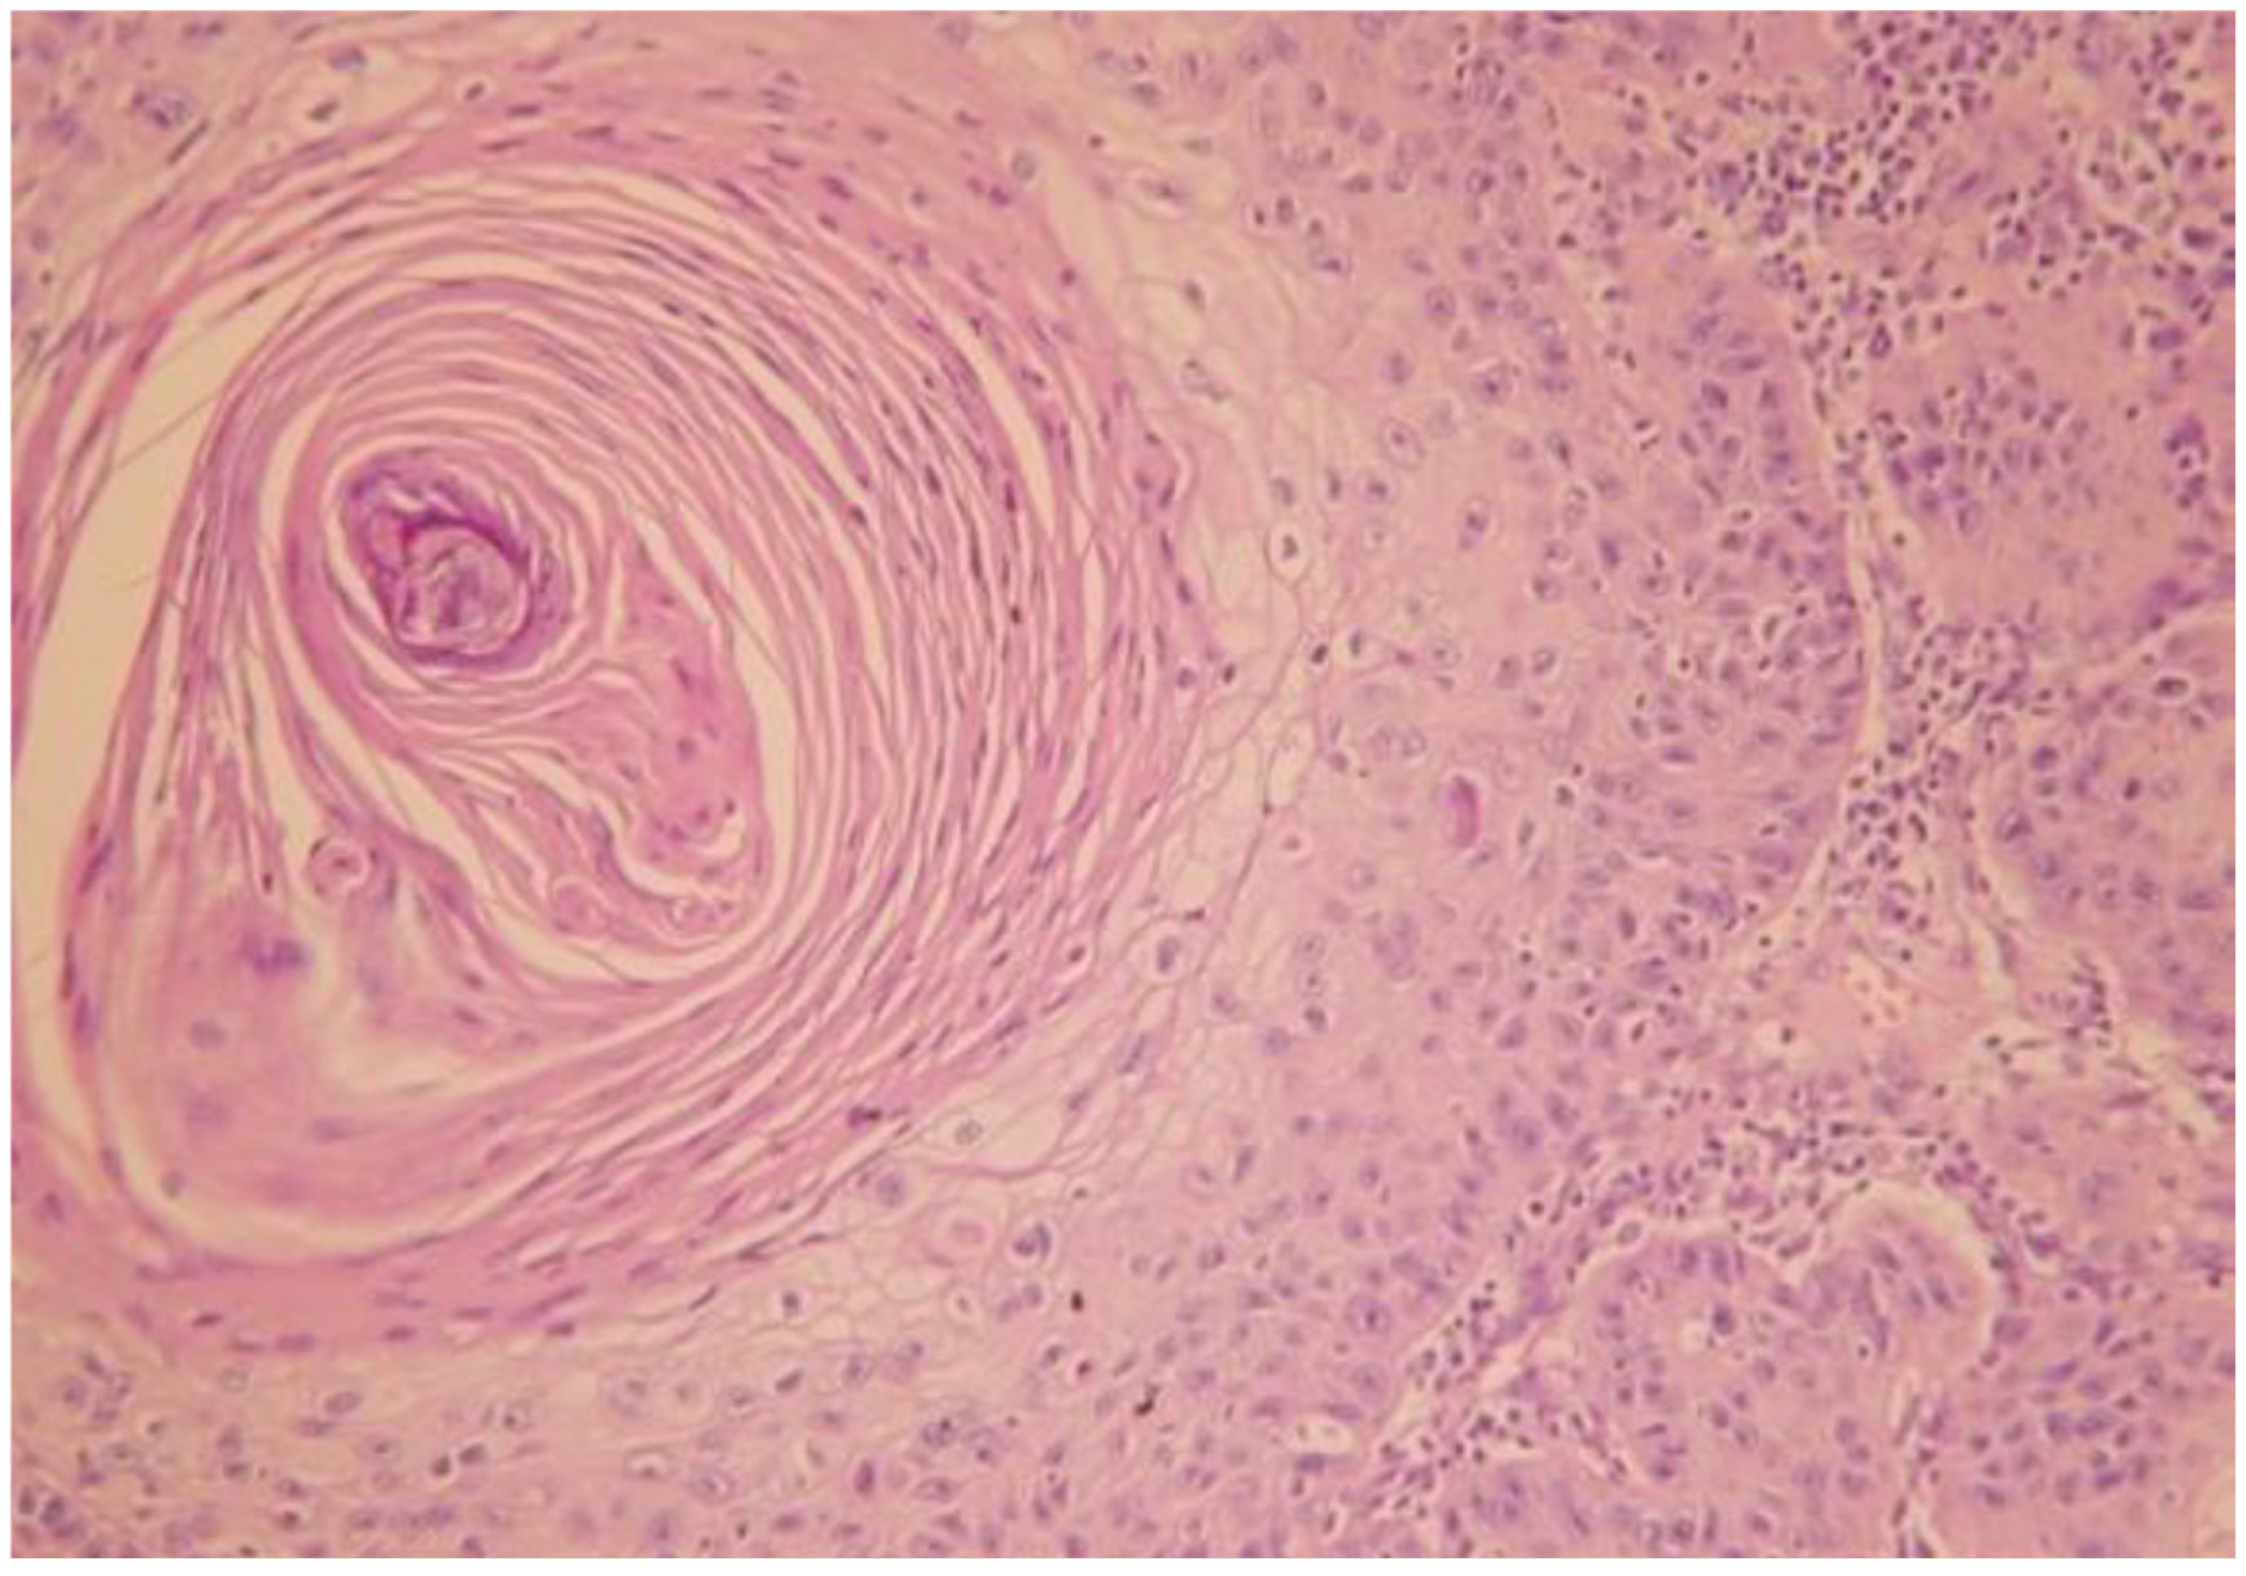

3.1. Case of a 74-Year-Old Female Patient

- Case 1-AI-Suggested AI Further Development